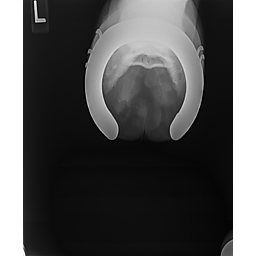

**Tex sells at the Colorado Horse Sale's Best of the West Select Sale on May 30th in Castle Rock, CO - He will complete the riding & handling Sift Exam, baseline veterinary exam, and will sell with 4 total radiographs (DLPMO & Front Foot Lateral)**